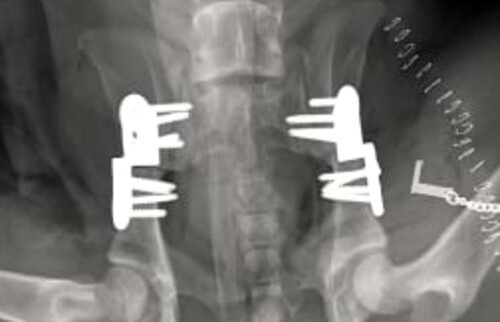

Bild einer beiderseitigen DPO.

Abb. 1: Bild einer beiderseitigen DPO.